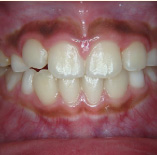

セラミック治療

こんな歯並びでもご心配なく。矯正という方法をとらなくても、ここまできれいに治せるんです。見た目だけでなく歯ブラシもやり易くなりました。笑顔に自信がつきますよ。

- 施術前

- 施術後